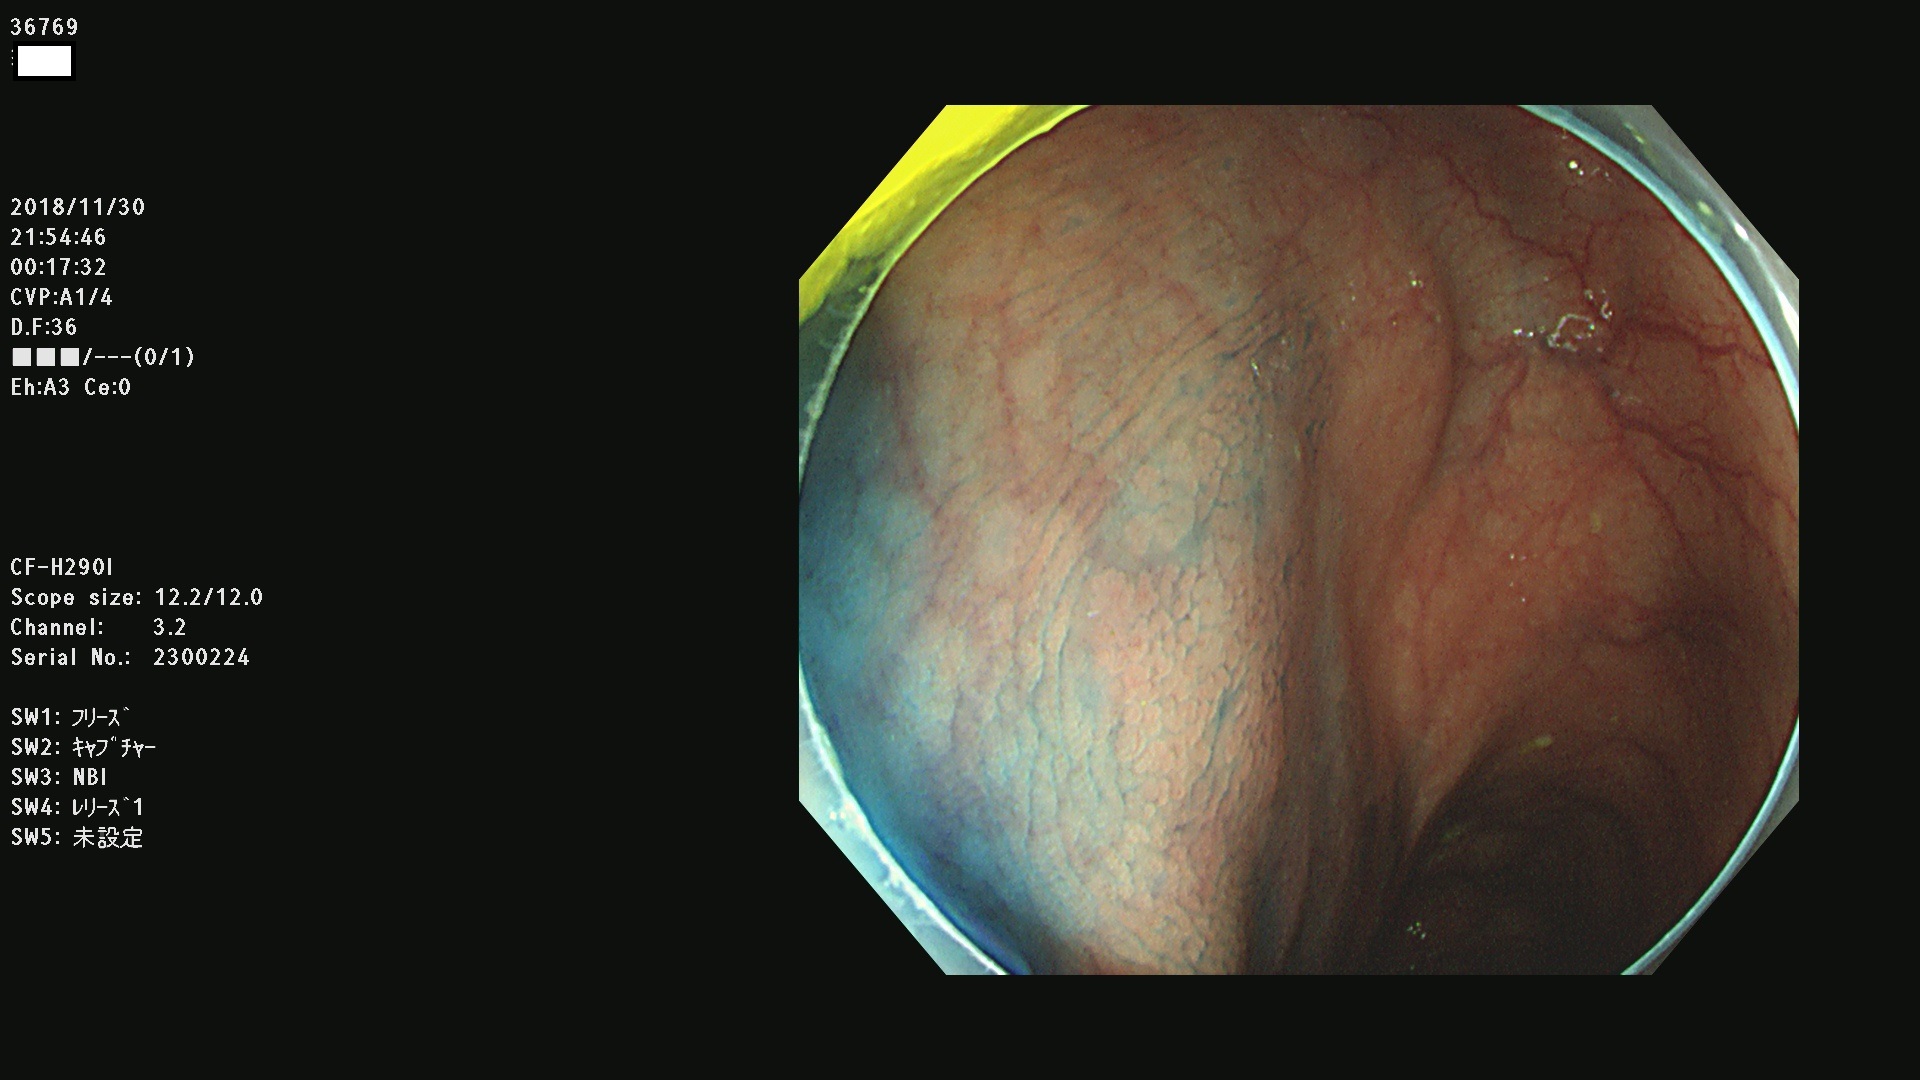

発見困難で危険性の高い平坦型病変(上記100名より抽出)